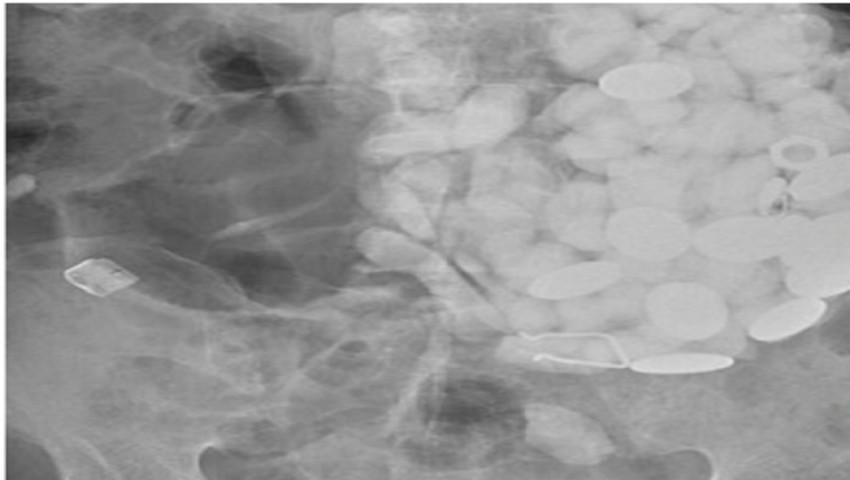

Un bărbat s-a prezentat la spital cu dureri acute de stomac și vărsături, iar după ce l-au examinat, medicii au avut parte de un adevărat șoc.

Bărbatul, în vârstă de 54 de ani, din Coreea de Sud, avea peste două kilograme de pietre și capace de plastic în stomac, motiv pentru care abia se mai putea mișca din cauza durerilor.După operație, bărbatul le-a mărturisit cadrelor medicale că a ingerat acele obiecte pentru a se trata de anxietate."N-am avăzut așa ceva toată cariera mea. De obicei extragem din stomac oase de pește sau pui. Mai rar ca cineva să înghită pietre în mod voluntar.", a declarat doctorul Choi, potrivit Mirror.co.uk.sursa